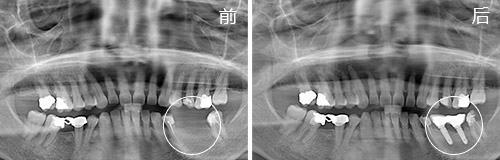

因为刷牙比较马虎,口腔清洁不力造成多颗牙齿蛀牙,部分做了补牙和固定修复,左下颌的磨牙由于没能及时修复而缺失。佩戴活动假牙一天之内要反反复复掉好几次,无法畅快吃一顿饭。

种植情况:种植2颗

种牙时间:2014年11月(已种牙1年9个月)